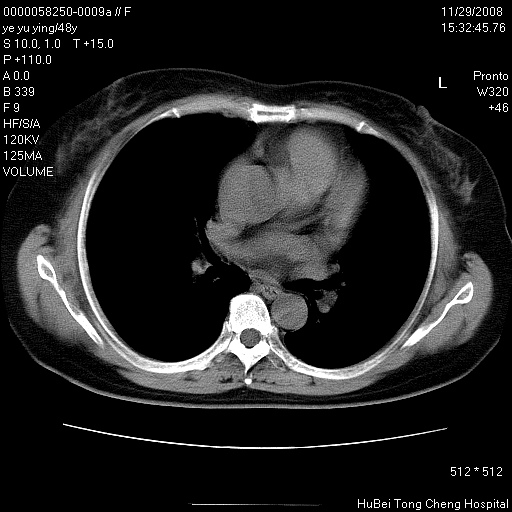

以下是引用zsl6918在2008-11-29 21:47:00的发言:[br]恶性肿瘤病史,转移瘤首先考虑。脂肪肝,胆囊结石。

以下是引用huenhao在2008-11-29 22:11:00的发言:[br]脂肪肝,胆囊结石。左肺病灶建议定期复查。

以下是引用liuyue在2008-11-30 5:44:00的发言:[br]1.左肺病变,首先考虑感染性病变,转移待排;建议治疗后复查。[br]2.肝脏密度普遍减低,考虑与化疗有关。[br]3.胆囊结石.